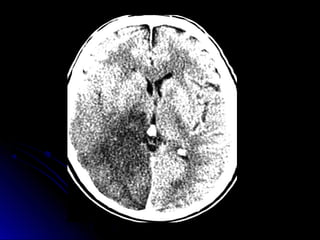

• 34.

Ubicación de laslesiones en TAC-RNM